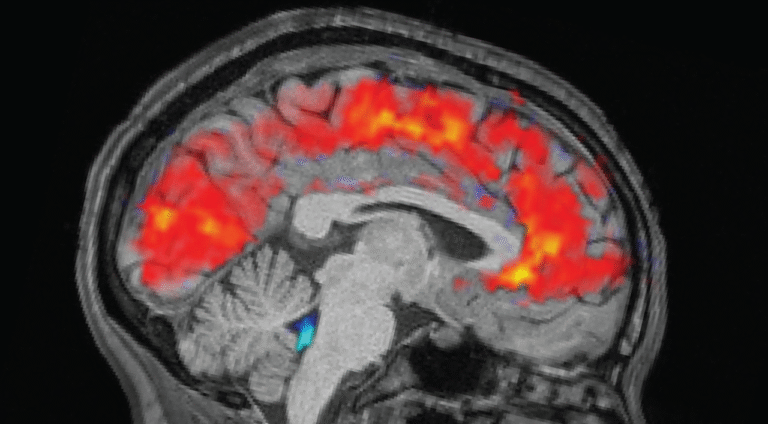

The rested individuals slept for 6.5 to 9 hours at home, while sleep-deprived individuals were kept awake all night in the laboratory. In the morning before each trial, the team strapped electroencephalogram (EEG) caps onto the participants to record their brain waves with electrodes. Simultaneously, the participants underwent functional MRI (fMRI) scans to reveal patterns in blood and CSF flow in the brain. Eye-trackers measured the participants’ pupil size.

As expected, participants took longer to notice the stimuli when tired, and missed the cues more often than they did when they were well rested. But the team was surprised to see giant pulses of CSF in the exhausted individuals, alongside patterns of slow brain waves — both of which are normally observed in non-REM sleep.

Specifically, the patterns resembled that seen as a person shifts from stage N1 into N2, the first two of three stages of non-REM sleep that people experience each slumber. “This was something that previously we’d only seen on this scale during sleep,” Lewis said.